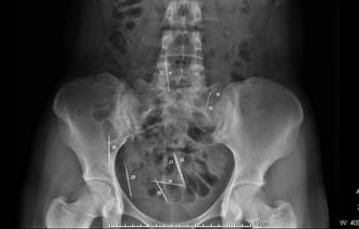

Ini adalah gambar sinar-x selangkangan juara Tour de-France, lance armstrong.